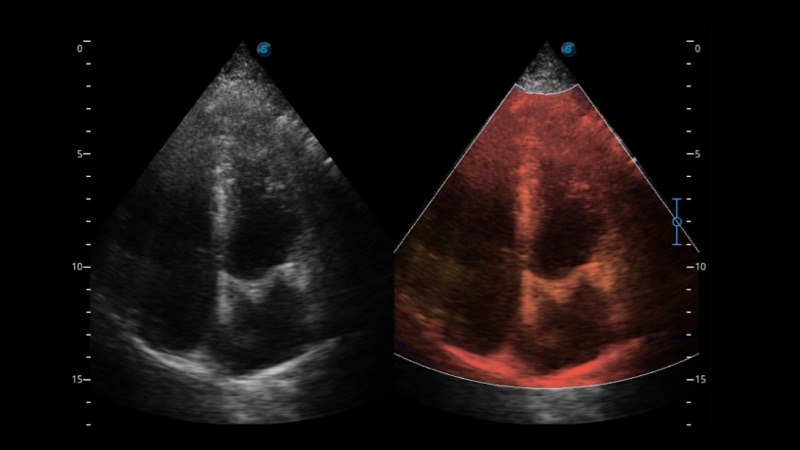

μ-Scan+新一代微米成像技术

新一代微米成像技术大大提高了器官和病变的可见性。高清对比度分辨率将抑制斑点噪声,同时保持真实的组织结构。

组织多普勒

组织多普勒成像功能,可提供心肌运动速度和其他临床信息,使临床医生能够分析和比较患者心脏不同部位的运动。

临床图像